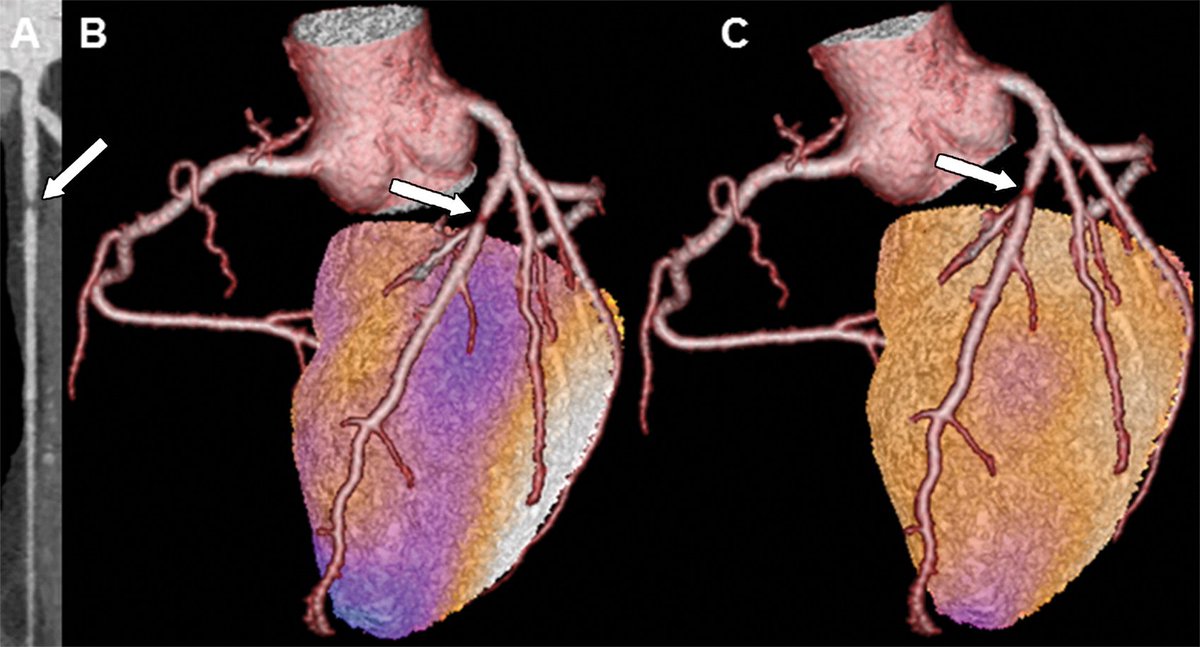

Johns et al assess interventricular septal angle in identification of combined per- and postcapilary pulmonary hypertension in patients with pulmonary hypertension due to left heart disease. http://ow.ly/XfLp30kPLi4 pic.twitter.com/NmmCIR523j